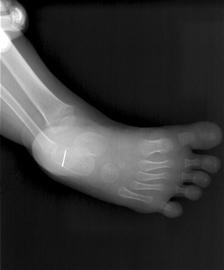

一枚1.5厘米长的断针,让2岁女孩诺诺受了罪。10天前,在家中玩耍的诺诺踩在线团上,一下被插在线团上的缝衣针扎入右脚跟,断针始终残留在诺诺脚跟的软组织里。虽然辗转多家医院,但断针始终没能取出,诺诺每天都承受着剧烈的疼痛,诺诺的父母也备受煎熬。昨天下午,诺诺终于进行手术,医生把“害人”的断针取出。

虽然异物小,但手术难度却很大。郝希伟说:“断针很小,通过CT来看,仅有1.5厘米左右。再加上针太细,体积小,手术探查时断针极易挪动,因此很难一次找准位置,这就增加了手术难度。 ”

下午2时,手术正式开始,出乎意料的是,诺诺的手术比较顺利,医生首先在她右脚底开了1厘米多长的刀口,经过仔细的手术探查后,顺利找到断针并确定了位置,随后医生用镊子将断针取出,整个手术耗时近1个小时。